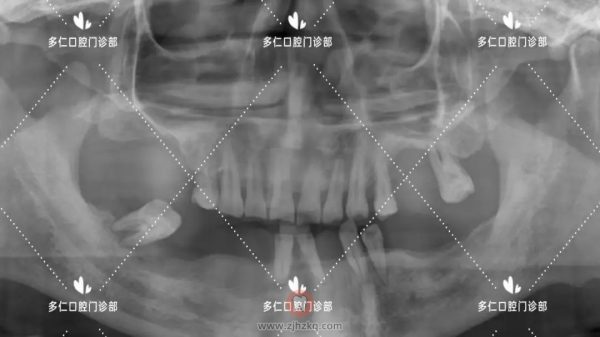

术前CBCT